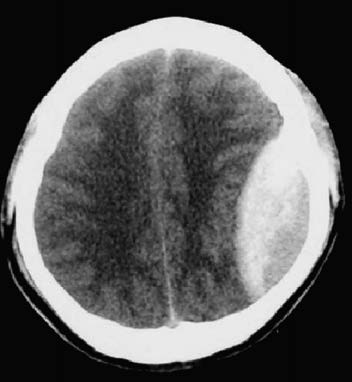

Figure 1 Epidural hematoma (CT, left parietal lobe)

CT scans not only provide direct visualization of the epidural hematoma, which appears as a biconvex or lentiform hyperdense lesion between the inner table of the skull and the dura, but also assess the degree of ventricular compression, midline shift, and coexisting cerebral contusions or edema. Early CT assessment and repeated scans as needed are essential after the injury.